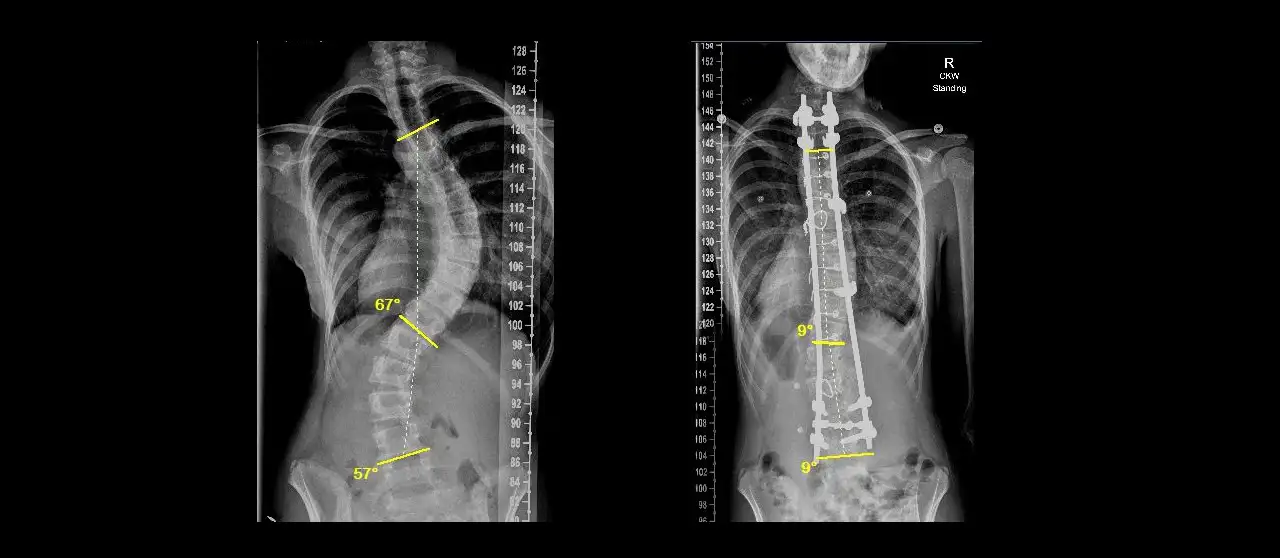

The procedures were quite complex, with each case requiring two surgeons working six to 10 hours in the operating room. “The local spine surgeons can do very good work, but only up to a certain limit. These were children they could not help because of the complexity of the deformities and the potential costs involved,” Parikh says.

Children with deformities this extreme require surgery or they risk becoming paralyzed before reaching early adulthood because the curvature of their spines can damage their spinal cords. The metal rods and implants they received will remain in their bodies for the rest of their lives.

Safely performing these operations requires expert surgeons, a highly skilled pediatric anesthetist, expensive implants and special neuro-monitoring equipment. Parikh spent more than four months organizing just such a team.

The children who received treatment ranged from age 3 to 14. To take on these cases, the local hospital created a temporary pediatric intensive care unit staffed by local pediatricians 24-hours-a-day to provide post-op care. Local spine surgeons will perform follow-up procedures on the youngest patients to lengthen the spine implant rods as the children grow.